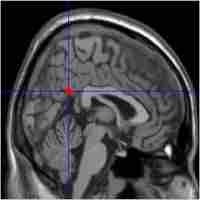

| Abstract | Mild cognitive impairment (MCI) is a transitional stage between normal aging and Alzheimer's disease (AD). Recent functional imaging studies have demonstrated regional deactivation magnitudes changes of default-mode network (DMN) in patients, accompanied by a defect of memory function. However, functional connectivity in the DMN during task performance was rarely investigated. METHODS : 26 amnestic MCI and 27 healthy controls underwent functional magnetic resonance imaging (fMRI) during an episodic memory task. Resting-state fMRI data were also collected. The changes in default-mode networks under both task-related and resting-state fMRI were obtained with a temporal correlation analysis. RESULTS: Significantly decreased functional connectivity was found mainly in anterior-posterior connectivity of DMN in aMCI groups. And a correlation existed between the anterior-posterior functional connectivity and MMSE scores. CONCLUSIONS: This study showed that disconnectivity of DMN could be used as an imaging biomarker for predicting the future cognitive decline of aMCI patients. |